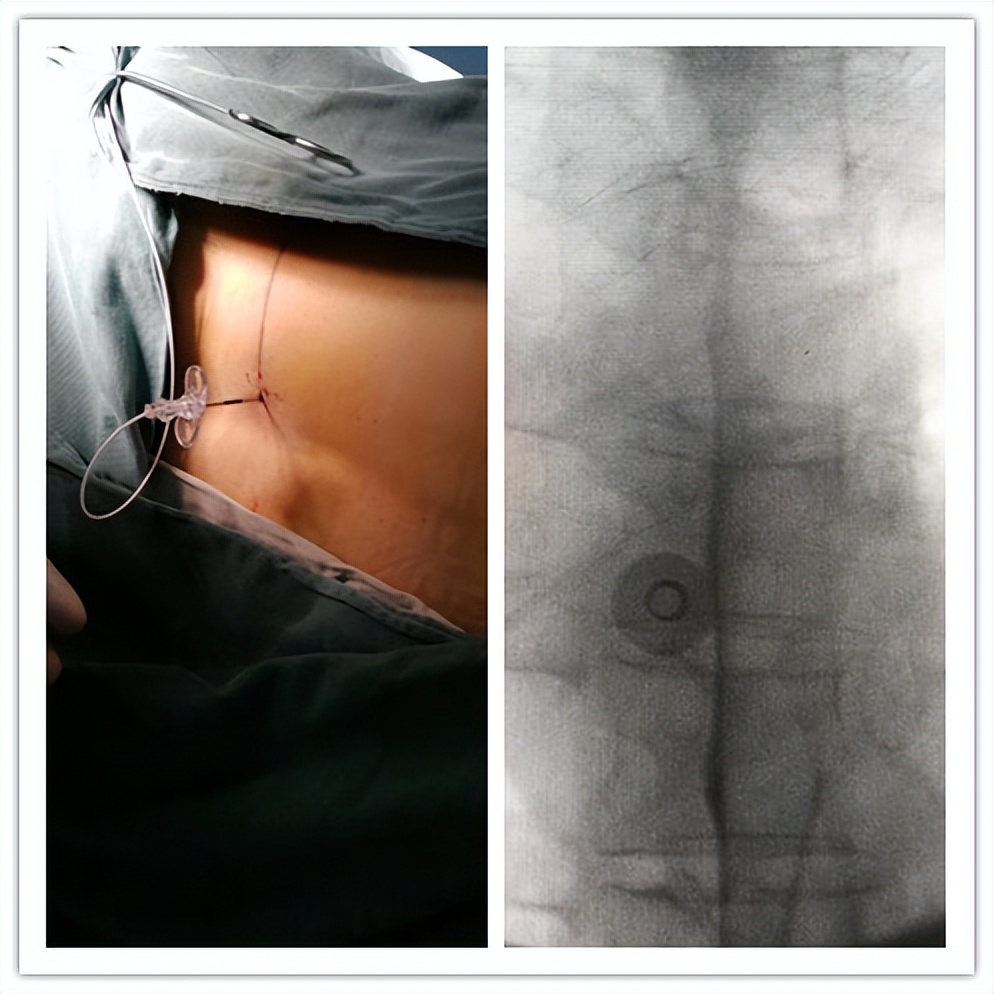

(晚期癌痛:*啡吗**泵置入)